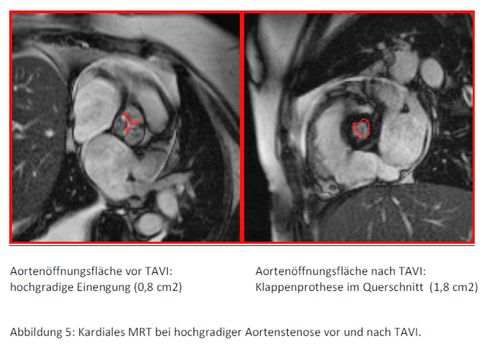

Je nach vorhandenen Vorbefunden werden hierfür ein Ultraschall des Herzens, eine Computertomographie bzw. MRT des Herzens und ein Herzkatheter benötigt. Eine akribische Befunderhebung ist zwingende Voraussetzung für die richtige Auswahl des Therapieverfahrens als auch für den Erfolg des Eingriffes selbst. Hierfür stehen in unserer Klinik alle modernen kardiologischen Untersuchungsverfahren zur Verfügung und werden von erfahrenen Ärzt:innen sorgfältig durchgeführt. Auf Grundlage der erhobenen Befunde wird geprüft, ob die Patient:innen technisch für die Prozedur in Frage kommen, welcher Klappentyp verwendet wird und über welchen Zugangsweg (Leistengefäße, Schlüsselbeinarterie oder Herzspitze) der Eingriff vorgenommen wird. Jeder Fall wird in unserer interdisziplinären Klappenkonferenz vorgestellt und eine Übereinkunft zum weiteren Vorgehen gebildet.

Im Jahre 2006 wurde weltweit die allererste kathetergestützte perkutane Herzklappenimplantation (TAVI) von Alain Cribier in Rouen durchgeführt, wodurch ein neues Zeitalter der Therapie der Aortenklappenstenose eingeläutet wurde. Seither hat eine rasante Entwicklung dieser Technik stattgefunden, die zu bemerkenswerten Ergebnissen geführt hat. Mit diesem Verfahren können jetzt auch Patient:innen mit hohem Operationsrisiko behandelt werden, die bisher als inoperabel galten. Dabei wird über eine spezielle Kathetertechnik über die Beinschlagader oder die Herzspitze eine neue biologische Herzklappe an Stelle der alten erkrankten Klappe eingesetzt. Hierdurch können ein großer Brustbeinschnitt sowie der Einsatz einer Herz-Lungen-Maschine vermieden werden. Insgesamt ist die kathetergestützte Implantation einer neuen Herzklappe für das Kollektiv der Hochrisikopatient:innen weit schonender und mit einem geringeren Risiko verbunden. In einer Studie mit ausgewählten, besonders stark erkrankten (und somit konventionell nicht operablen) Patient:innen konnte die Ein-Jahres-Sterblichkeit von 50,7% (ohne OP) auf 30,7% (Katheterverfahren) gesenkt werden.